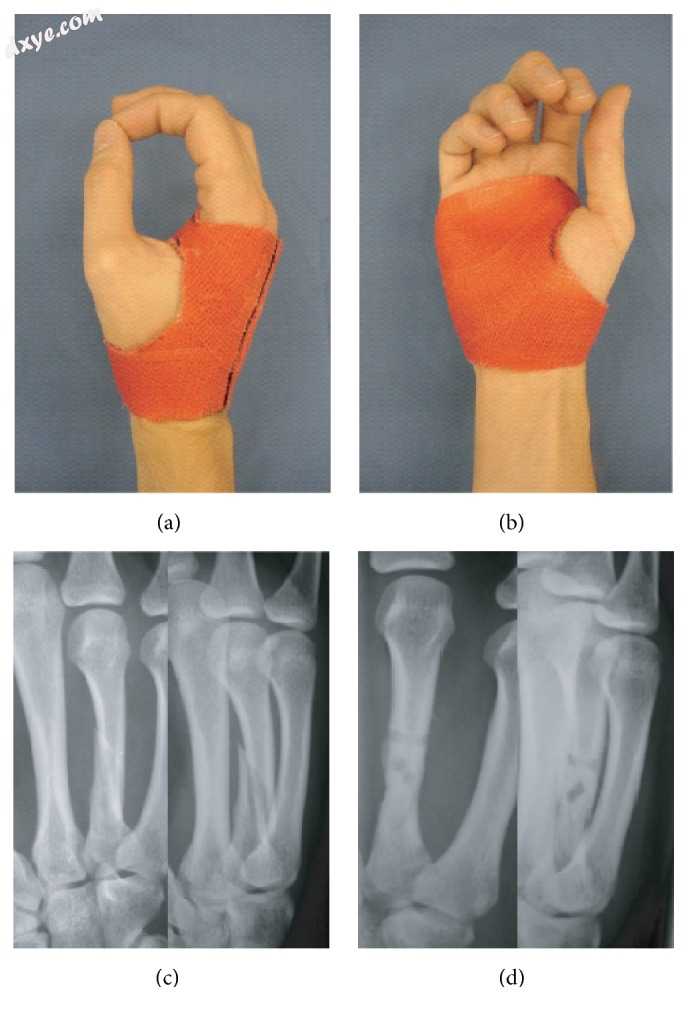

拇指矫形器:(a)背部和(b)手掌视图和(c)病例样本:骨性尺侧副韧带创伤性损伤后佩戴矫形器后6周的X射线(病例系列的DASH分析:n = 11;评分均值 = 29.9±1.73 SD; DASH随访间隔(周):9.5±2.01 SD)。

样本案例。 拇指的尺骨或桡侧副韧带的非定位骨性撕脱通常可以在不进行手术的情况下进行治疗[11](图2)。